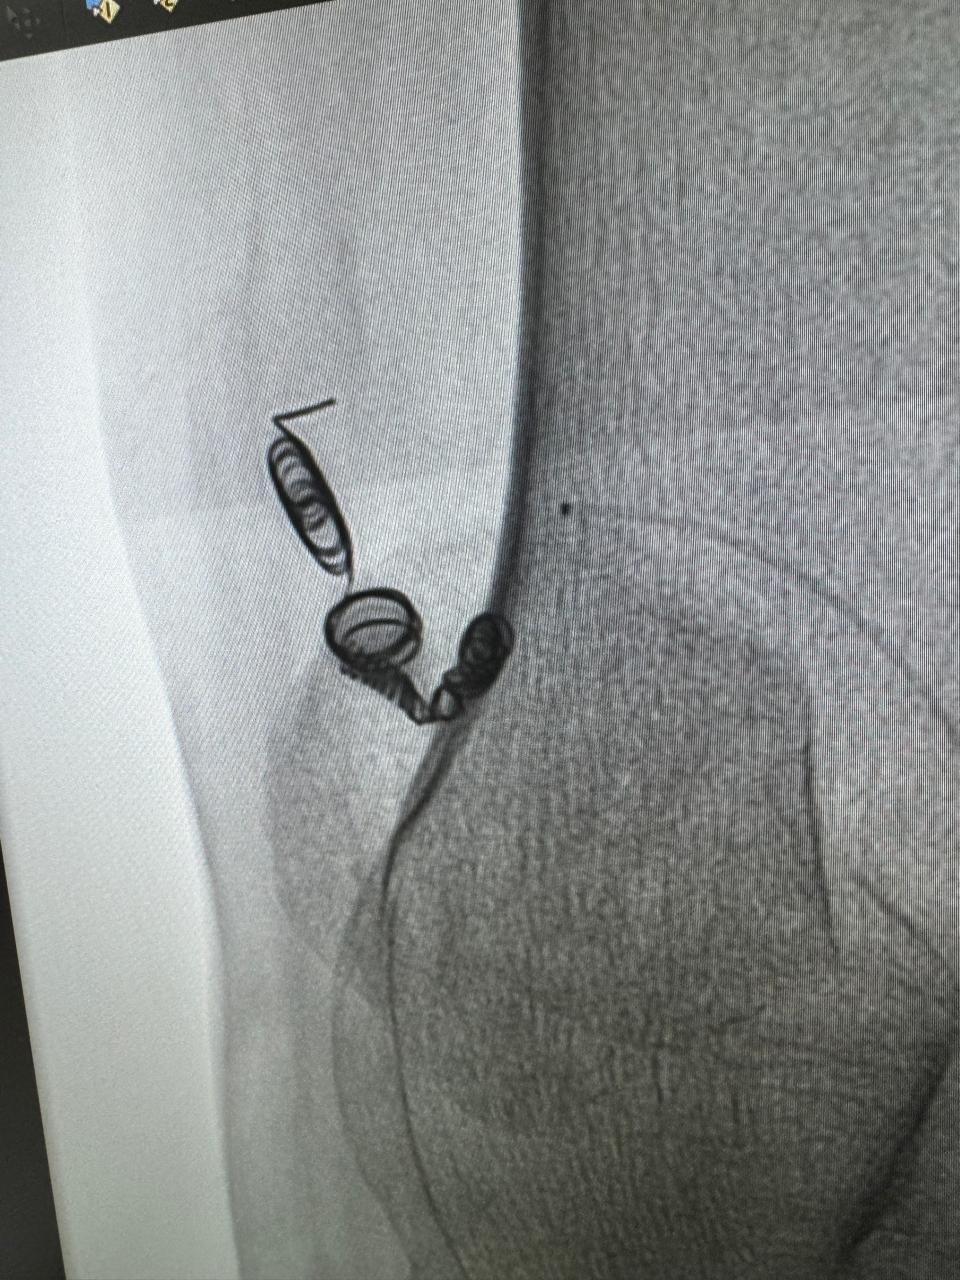

Vascular embolization of arteriovenous malformation

Angioembolization of traumatic right internal iliac artery ( posterior branch)injuries